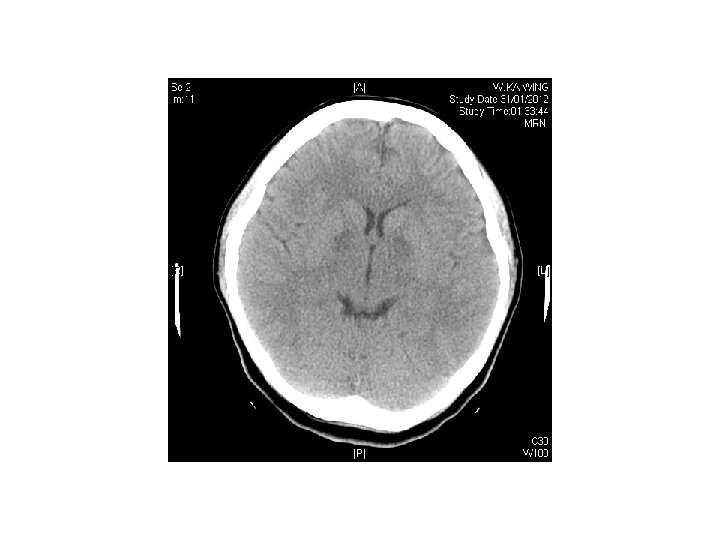

Case 5 • F/25 • She attempted suicide by burning charcoal at home • PE: GCS 14/15, BP 98/73 mm. Hg, Pulse 83/min, Sa. O 2 99% on 100%O 2 • Systems review were unremarkable. No focal neurological sign elicited.

Question • 1) describe the CT findings • 2) what is the diagnosis? • 3) what is the management?

Answers • Symmetrical hypodensity noted at bilateral basal ganglia • Compatible with CO poisoning • Rx : stabilize ABC • Administer 100%O 2 via tight fitting face mask • Intubate and provide IPPV on 100%O 2 if unconscious

• Record ECG, check ABG, COHB level • Consider hyperbaric oxygen therapy if • COHB >25%, pregnant patients with COHB >10%, myocardial ischemia, worsening symptoms despite oxygen therapy, all patients with syncope, neurological or cardiac abnormalities with elevated COHB